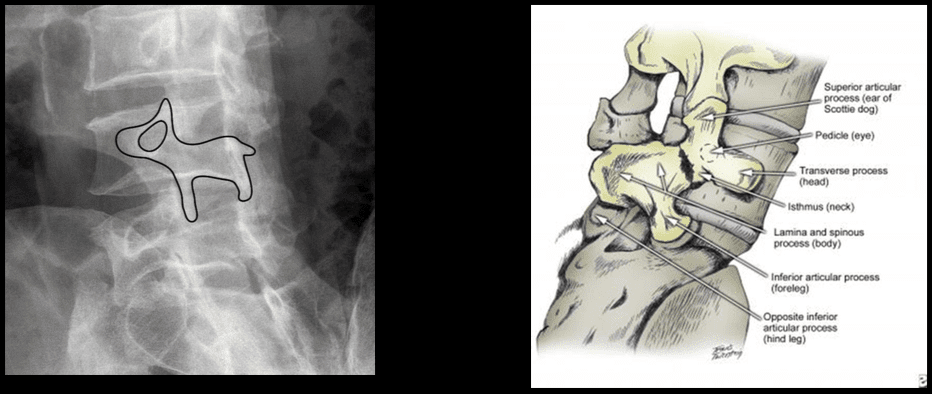

L-uġigħ u t-tenerezza lokalizzata fis-sinsla assjali ġeneralment toriġina min-nociceptors misjuba fid-diski intervertebrali, il-ġogi tal-faċċati, il-ġogi sacroiliac, id-dura tal-għeruq tan-nervituri, u l-istrutturi miofaszjali li jinsabu fl-ispina axial. Kif issemma fit-taqsimiet ta 'qabel, il-bidliet anatomiċi deġenerattivi jistgħu jirriżultaw fi tidjiq tal-kanal tas-sinsla msejjaħ stenożi spinali, żieda żejda ta' proċessi spinali msejħa osteofiti, ipertrofija tal-proċessi articulari inferjuri u superjuri, spondilolistesi, tixrid tal-ligumum flavum u herniation disk . Dawn il-bidliet jirriżultaw f'ġabra ta 'sintomi li hija magħrufa bħala claudication newroġenika. Jista 'jkun hemm sintomi bħal uġigħ fid-dahar baxx u uġigħ fir-riġlejn flimkien ma' tnemnim jew tingiż fis-saqajn, dgħjufija fil-muskoli, u qatra fis-saqajn. It-telf ta 'kontroll tal-musrana jew tal-bużżieqa jista' jissuġġerixxi l-imġieba tad-dahar tas-sinsla u hemm bżonn ta 'attenzjoni medika fil-pront biex jiġu evitati diżabilitajiet permanenti. Dawn is-sintomi jistgħu jvarjaw fis-severità u jistgħu jippreżentaw diversi estensjonijiet f'individwi differenti.

Il-marda deġenerattiva tad-diska għandha diversi dijanjosi differenzjali li għandhom jiġu kkunsidrati meta pazjent jippreżenta uġigħ fid-dahar. Dawn jinkludu; uġigħ fid-dahar idjopatiku, deġenerazzjoni tal-ġogi zygapophyseal, majelopatija, stenożi tal-ġenbejn, spondilosi, osteoartrite, u radikulopatija tal-ġenbejn. ("Marda tad-Diska Deġenerattiva" Fiżjopedja)